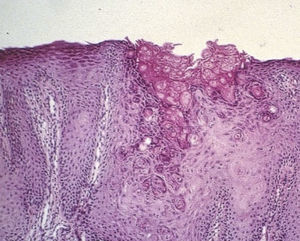

El signo de Leser-Trélat se caracteriza por la aparición súbita y el rápido crecimiento en número y tamaño de múltiples queratosis seborreicas, relacionado con una neoplasia subyacente. Masculino de 57 años de edad, con 4 meses de evolución con cambios en hábitos defecatorios, refiriendo adelgazamiento de las evacuaciones, así como la presencia de rectorragia ocasional con manchado lineal de las evacuaciones, asociado a esto refiere la aparición de hace un año de lesiones dérmicas en su espalda que aparecieron súbitamente y se incrementaron en número. En la colonoscopia con lesión circunferencial a 13cm del margen anal (fig. 1) con reporte histopatológico de adenocarcinoma. En la espalda del paciente (fig. 2), se aprecian múltiples lesiones dérmicas de las que se toma biopsia reportándose queratosis seborreica (fig. 3).

El signo de Leser-Trélat es definido como el inicio abrupto, con incremento rápido del tamaño o el número, de múltiples queratosis seborreicas asociadas a un cáncer. La presencia de lesiones de queratosis seborreica con aparición repentina, lesiones pigmentadas y en gran número deben de alertar al clínico para descartar otras entidades y asociaciones a otras lesiones como neoplasias. La biopsia de las lesiones dérmicas confirma el diagnóstico.